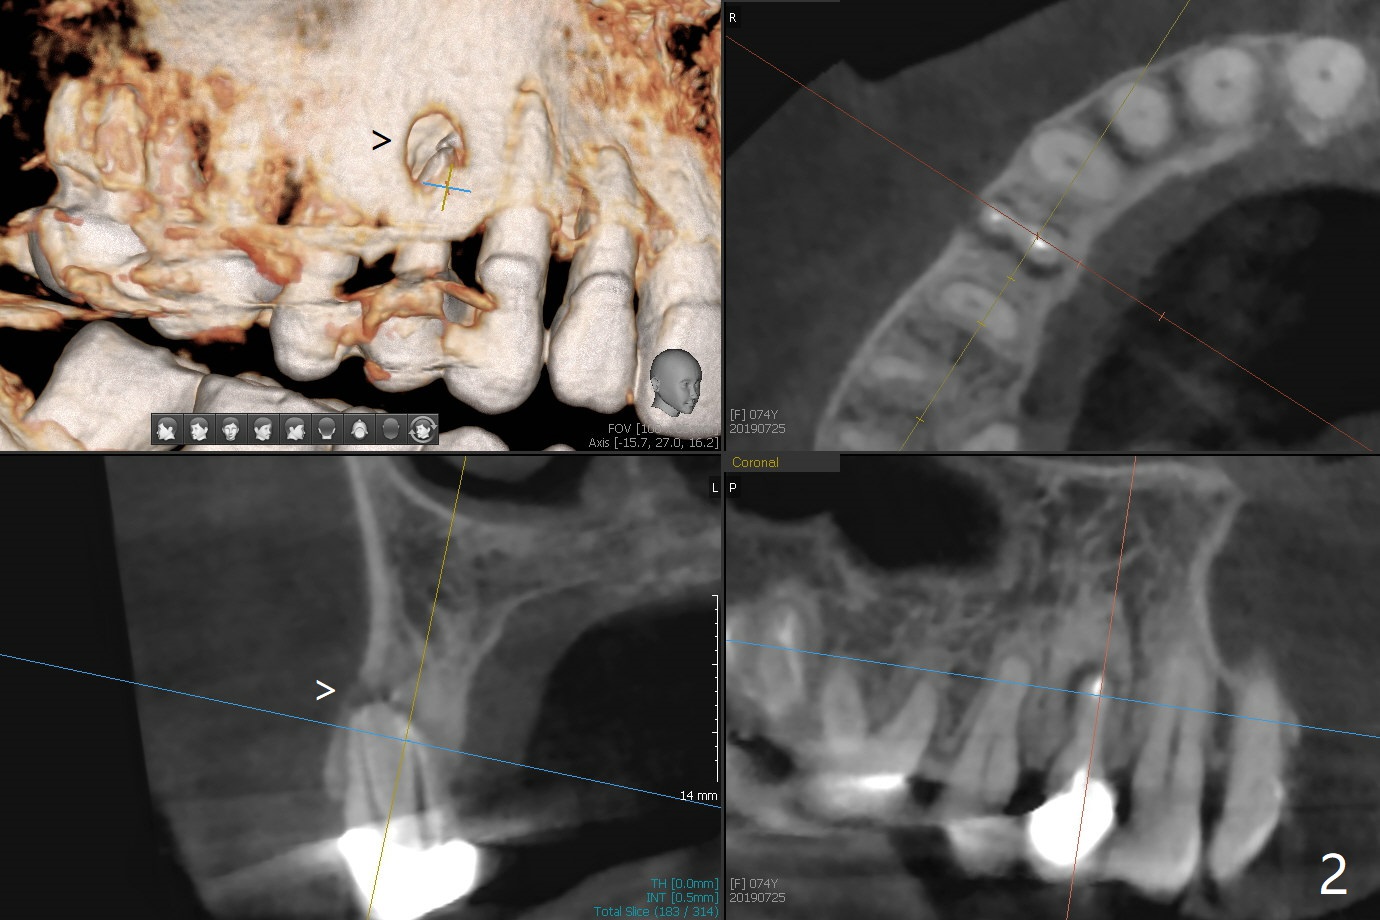

A 74-year-old woman is concerned about buccal fistula of the tooth #5 (Fig.1,2 >). It seems to be safe to place an immediate implant without too much possibility of developing periimplantitis in the future (Fig.3). With guide, restoration could be finished with a 15 degree angled abutment. Remove granulation tissue from the buccal fistula and from the socket. Place a piece of PRF membrane externally (tunnel incision, Fig.4-6 red line) or internally (from the socket) before bone graft (before and after implant placement (Fig.5,6 yellow circles)). Take 5x5 cm CT immediately postop to confirm the repair.